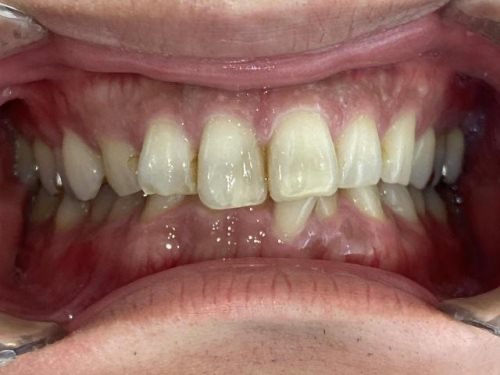

30代男性「噛み合わせが深く、下の前歯が1本だけ前に出ていて気になる」奥歯から歯を動かして前歯を並べるスペースを作る「インビザラインフル」で歯並びと噛み合わせを改善した症例

前に1本出ていた前歯は、しっかり歯列におさまりきれいな歯並びになりました。

過蓋咬合も改善し、正しい位置で噛み合わせられるようになりました。

患者様には「気になっていたことがどちらも改善されて嬉しいです」と大変喜んでいただき、笑顔がとても素敵になりました。